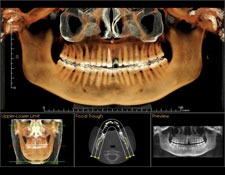

Tomografie computerizată dentară

Tomografia computerizată oferă imagini tridimensionale precise, fiind utilă pentru planificarea intervențiilor chirurgicale dentare complexe sau pentru evaluarea problemelor osoase.